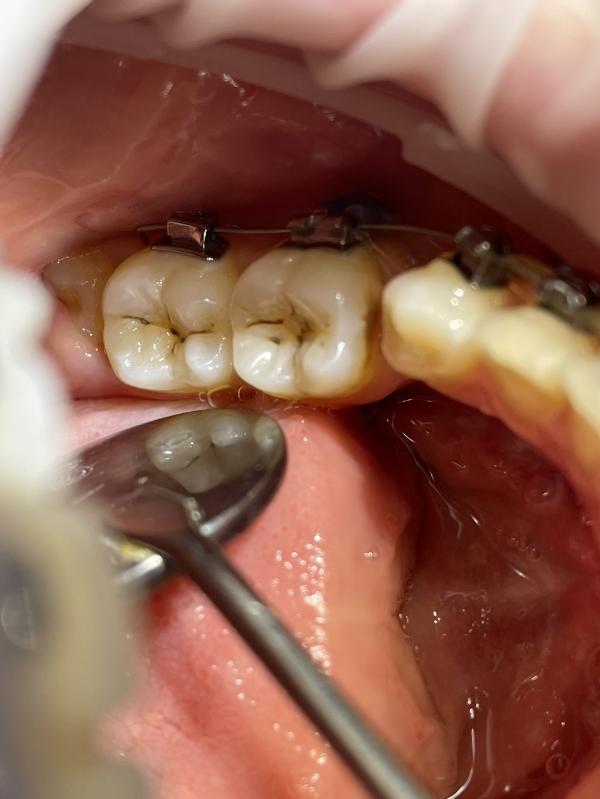

на фото представлено

Это кариес в области фиссур зуба, вот как на фото ( в углублениях черное то что вы видите) если не лечить такой кариес через 1/2 года зуб разрушается, появляются сильные боли, воспаляется пульпа(пульпит)